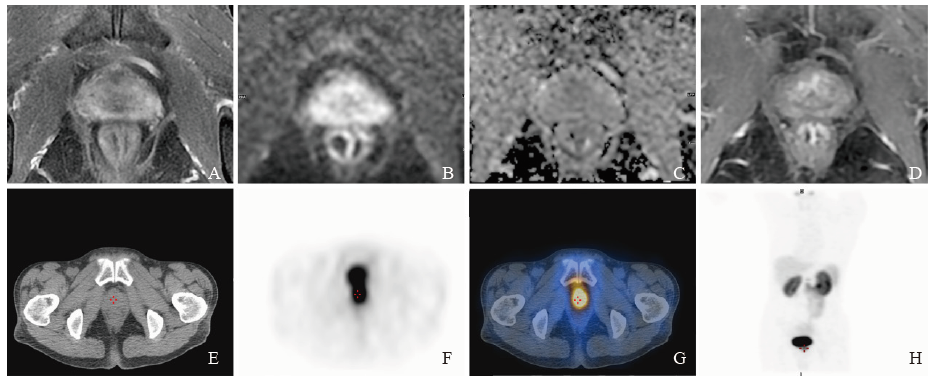

mpMRI combined with 99mTc-PSMA SPECT/CT to detect significant residual prostate cancer after neoadjuvant androgen deprivation treatment A 73-year-old patient received 3 months of neoadjuvant ADT with Gleason score 5+4=9, initial PSA was 82.56 ng/mL, PSA after neoadjuvant ADT was 5.73 ng/mL. Pathology diagnosis after RP confirmed the presence of significant residual lesion. A: The prostate showed heterogeneous signal intensity on T2WI, and the bilateral peripheral zone were diffuse moderate hypointensity; B, C: No obvious abnormal signal intensity on DWI and ADC images; D: No obvious abnormal enhancement lesion on DCE, PI-RR score 1; E: Cross-sectional view of the prostate on CT; F: Positive lesion was detected by SPECT; G: Fusion image of SPECT and CT; H: Maximum intensity projection image."